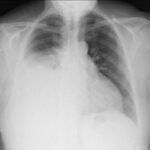

Desde el punto de vista radiológico, las radiografías de tórax suelen mostrar múltiples opacidades redondeadas con bordes bien definidos, localizadas habitualmente de manera bilateral, preferentemente en regiones pleurales o subpleurales y con mayor frecuencia en las zonas inferiores de los pulmones. No obstante, existen presentaciones menos frecuentes, como la diseminación linfangítica, que afecta los vasos linfáticos pulmonares, o la aparición de un nódulo pulmonar solitario, que también pueden corresponder a metástasis pulmonares.